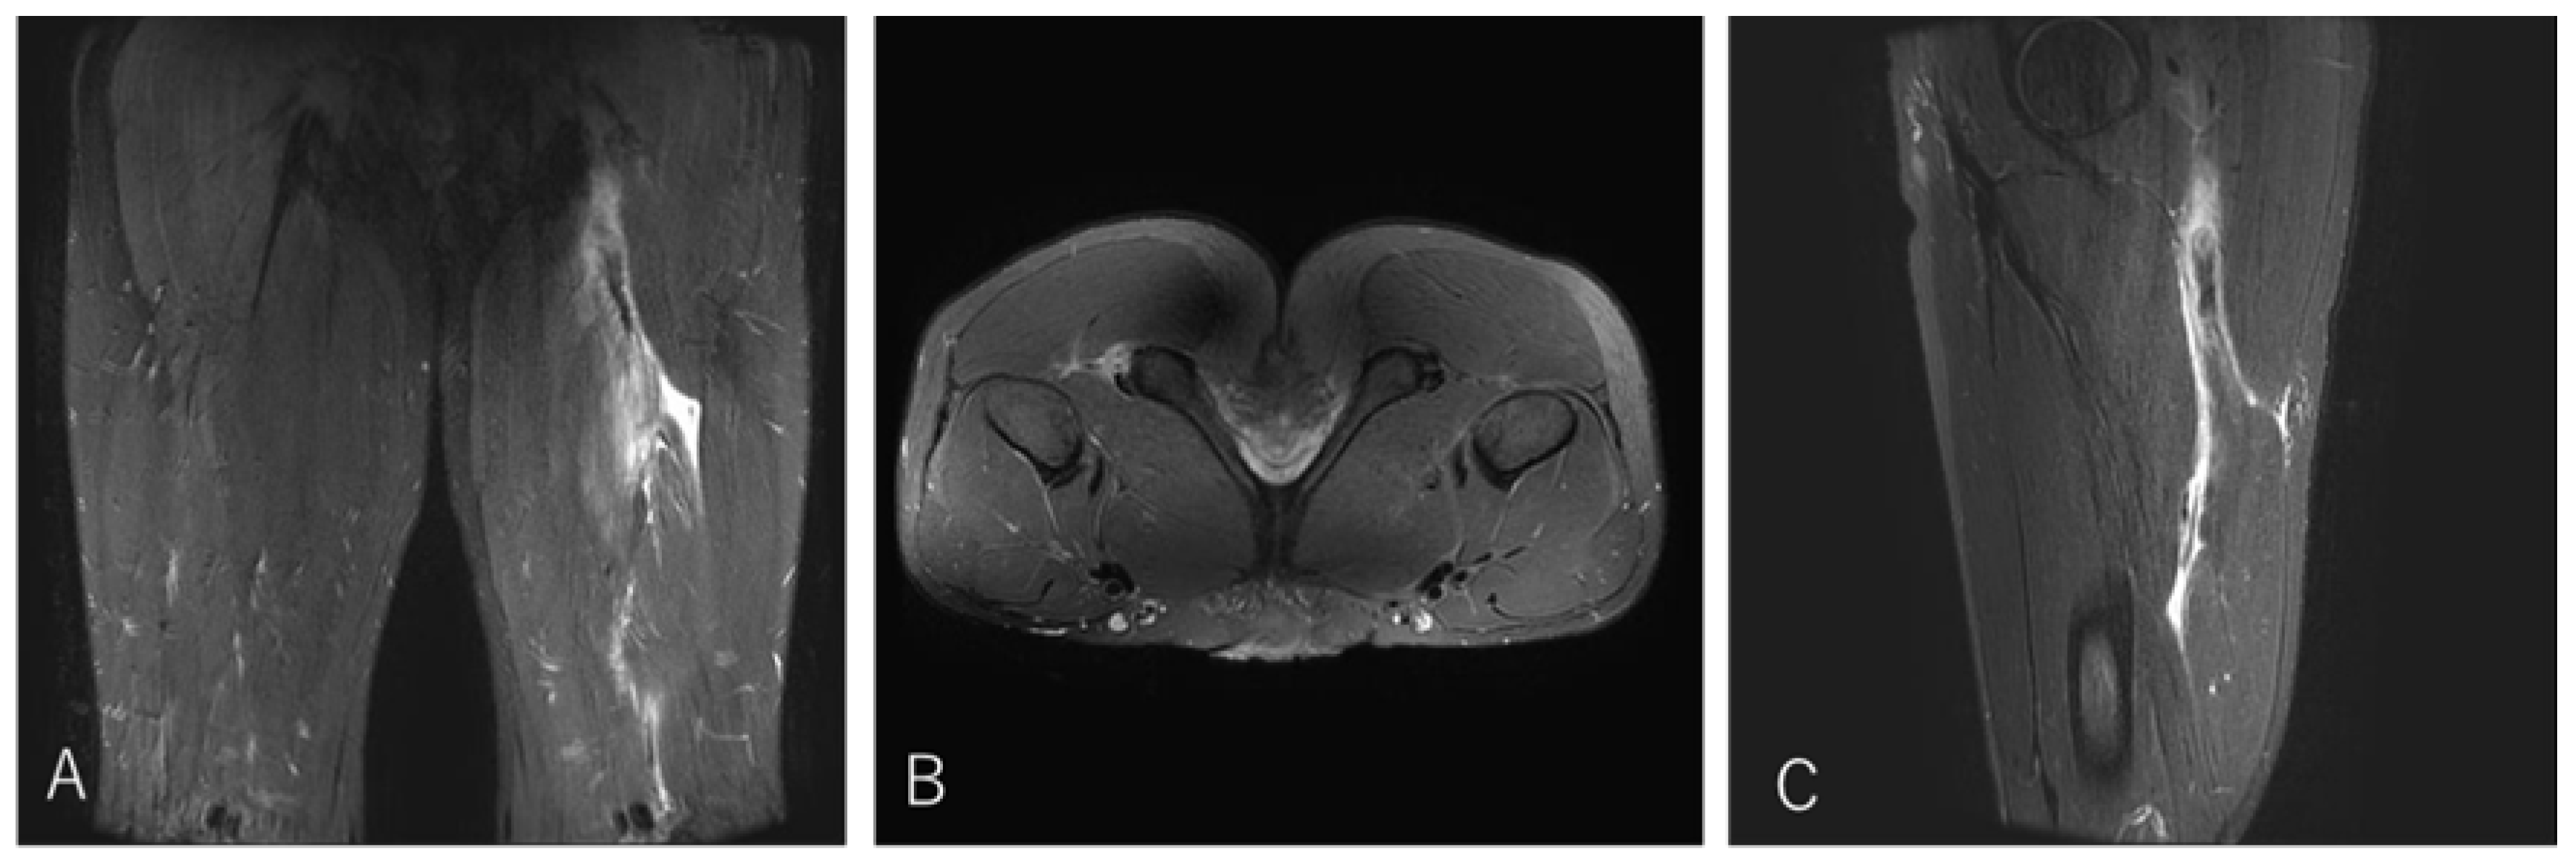

4.2. Case 2. Type I / Zone B (Conjoint tendon tear), Grade 3

A 20-year-old flanker (FW) experienced sharp twisting pain during a 30-m sprint drill while running at top speed. He returned to play after 14 weeks.

Figure 4. Case 2 MRI images: Conjoint tendon tear, Type I.

Preprints 186662 g004